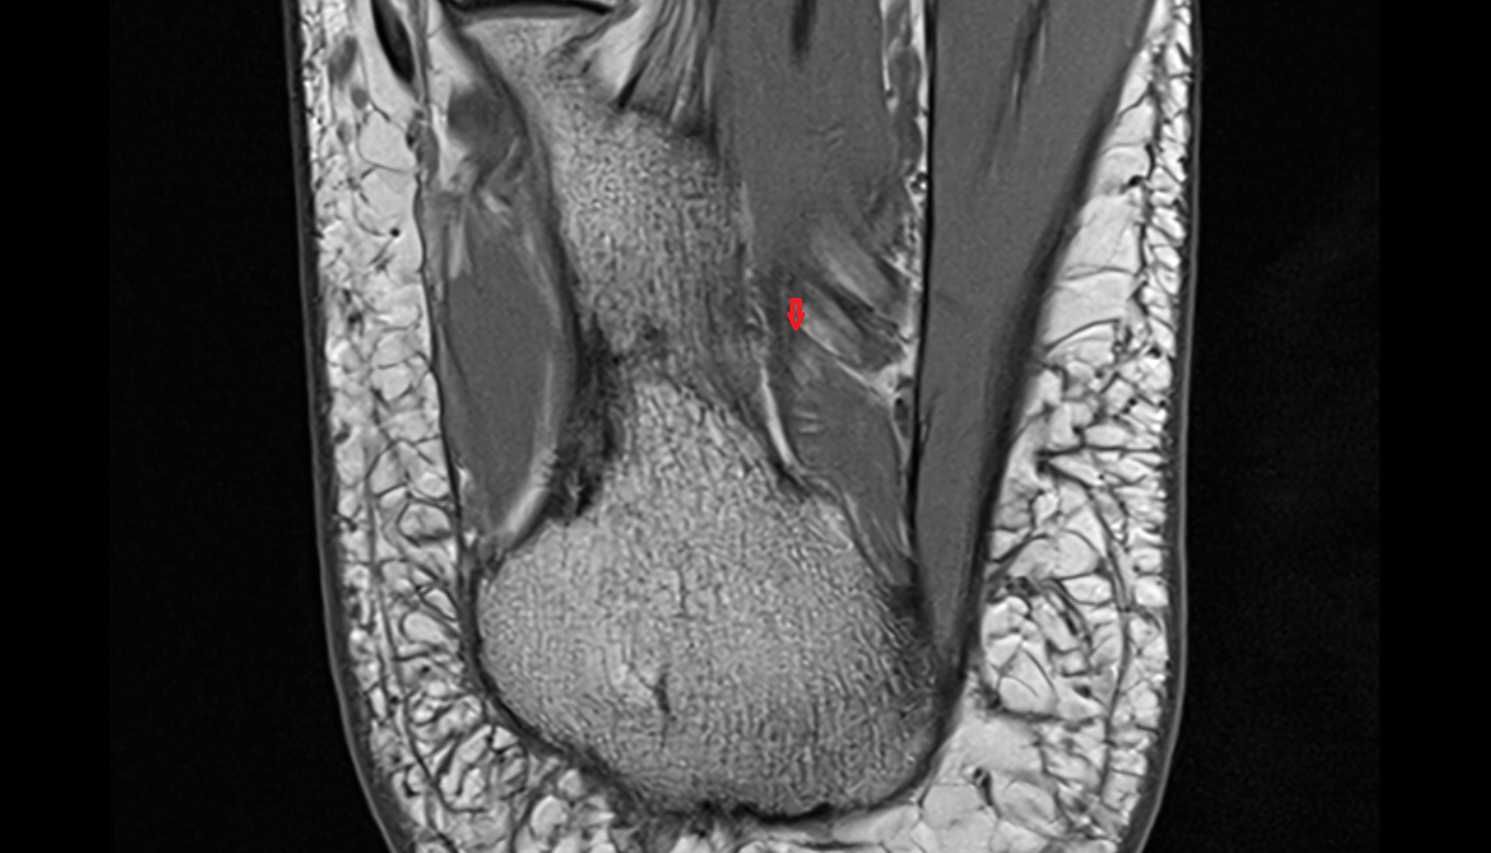

MRI images

Inferior calcaneal nerve (Baxter’s nerve) axial cross sectional anatomy 3T MRI AI enhanced radiology image-img-00000-00000_00002